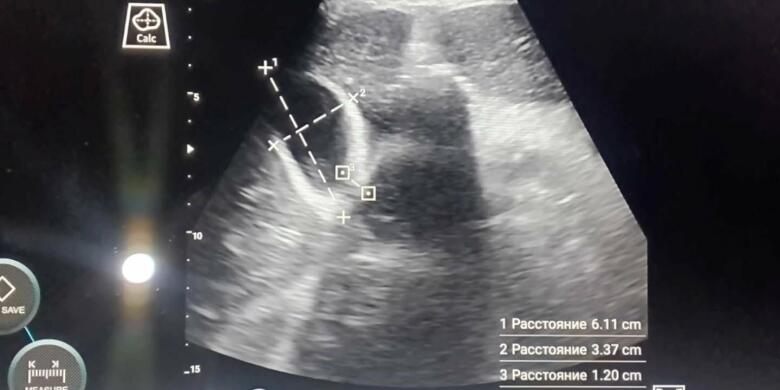

В Северо-Казахстанской области внедрена современная технология ультразвуковой диагностики в работу бригад скорой медицинской помощи, передает корреспондент 7152.kz. Год назад специалисты протестировали тренажерный комплекс УЗИ в Высшей школе медицины при СКГУ им. М.Козыбаева. После успешного тестирования было принято решение обучать врачей и фельдшеров основам УЗИ диагностики, а также приобрести портативные УЗИ сканеры для выездных бригад. «Сейчас можно ув...